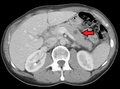

CT image of multiple liver metastases